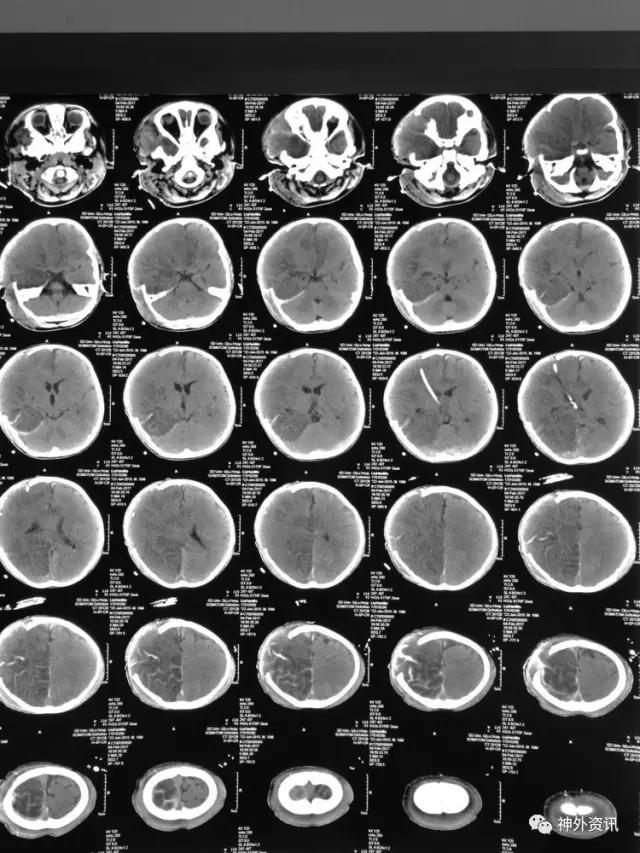

患儿刘**,男,19个月,2017.1.30 2pm不慎摔倒,意识障碍,刺痛不睁眼,不发音,刺痛肢体屈曲,急至当地医院,伤后1小时颅脑CT结果示右额颞顶枕急性硬膜下血肿,中线轻微左移:

3小时后转至我院急诊科,当时查体:刺痛不睁眼,不发音,刺痛右侧肢体屈曲,右侧瞳孔5mm,对光反应消失,左侧瞳孔0.3cm,对光反应迟钝,立即术前准备并复查CT,结果示右额颞顶枕硬膜下血肿,右侧大脑半球及左侧额叶弥漫性低密度,考虑缺血,中线左移明显,脑沟及环池显示不清:

术后移动CT结果示中线移位较术前减轻,顶枕部蛛网膜下腔出血:

2017.2.1:术后2天复查颅脑CT,结果示中线居中,右侧半球低密度并SAH,左侧半球未见明显异常,左侧脑沟可见显示,双肺少量炎症,不能放松警惕,继续同前治疗。

2017.2.4:术后5天复查颅脑CT,结果示中线居中,左侧半球及环池显示清晰,右侧半球脑沟显示欠清晰,脑组织低密度较前有所好转,继续同前治疗。已加用预消化肠内营养液及促进胃肠动力药物。

2017.2.6:术后7天,复查颅脑CT示情况较前进一步好转,逐步撤掉冰毯,缓慢自然复温。

2017.2.8:术后9天,复查颅脑及胸部CT,结果显示双侧脑沟脑回及环池显示清晰。颅压控制,拔除引流管探头,头部敷料稍加压包扎,此时已更替力月西为丙泊酚,停用呼吸机。